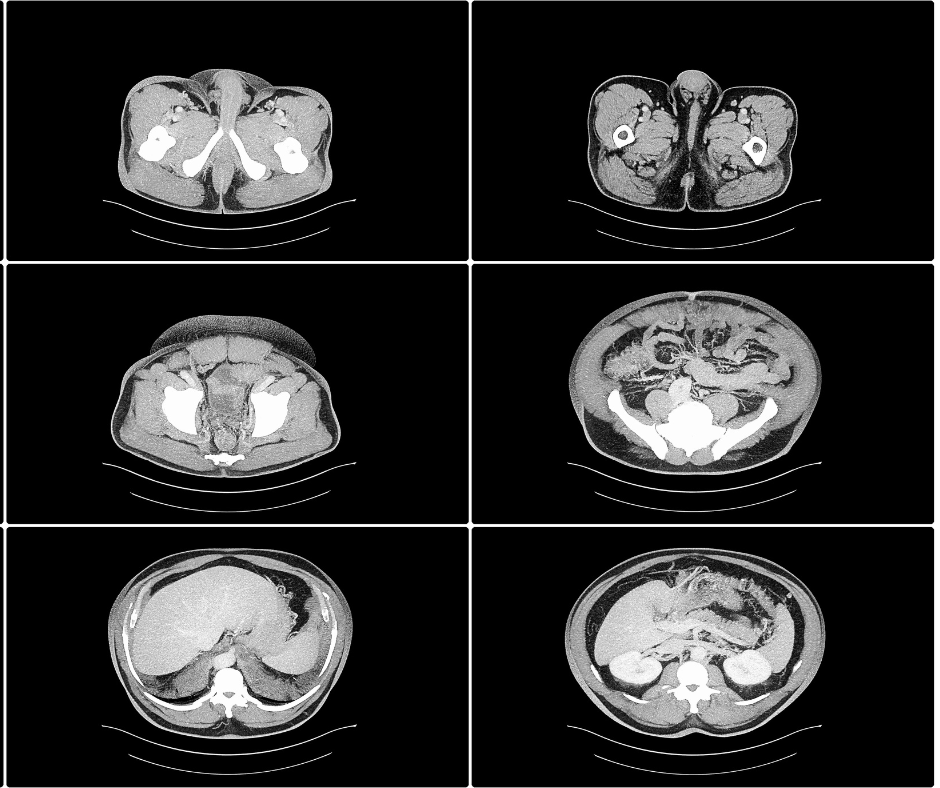

In a study involving 201 consecutive patients presenting to emergency departments (EDs) with abdominal pain, researchers found that radiology faculty accuracy rates in interpreting non-contrast, abdominopelvic computed tomography (CT) scans ranged from 68 to 74 percent.

A hybrid computed tomography radiomics model demonstrated up to an 86 percent area under the curve in predicting microvascular invasion in patients with hepatocellular carcinoma in a recently published study.